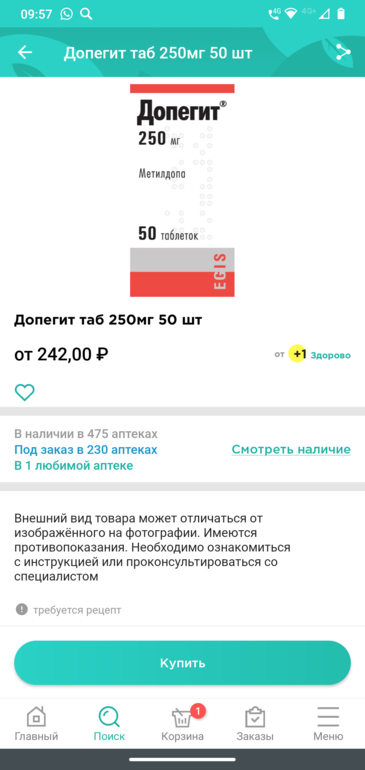

1)Узист смотрел доплер и я так поняла, ему что-то не понравилось в пике маточной артерии, он сказал - с кровотоками все хорошо, но есть риск развития приэклампсии. Я приэклампсии боюсь как огня, спросила что делать - контролировать давление, начать приём допегита, я спросила нужно ли сдать коагулограмму, он сказал, что если есть желание, то можно, но если до этого все ок было, то не обязательно. А коагулограмму я сдавала только в жк, там хрен разберешь 🤷🏻♀️

Допегит пить начну, но мы с ним заболтались и я так и не узнала по сколько пить 😅 бывают у меня подъёмы давления до 130/80, в жк то вообще конечно до 150/100,но через пару минут становится 120/80, но я лучше начну пить.